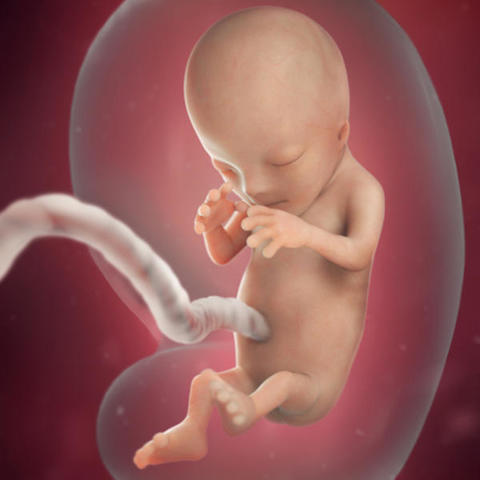

• Semana 9 - Inicia el periodo fetal

Semana 9 - Inicia el periodo fetal

Mide entre 17 y 22 milímetros. Y físicamente también ha cambiado mucho: la cola ha desaparecido y la cabeza se ha separado un poco del cuerpo gracias a un incipiente cuello que humaniza su silueta.

- Los ojos se acercan entre sí, mientras que los párpados empiezan a formarse y casi cubren los ojos. Ya ha aparecido el labio.

- Se forman los pezones y los folículos pilosos.

- Los brazos crecen y se desarrollan los codos.

- Se pueden observar los dedos del pie del bebé.